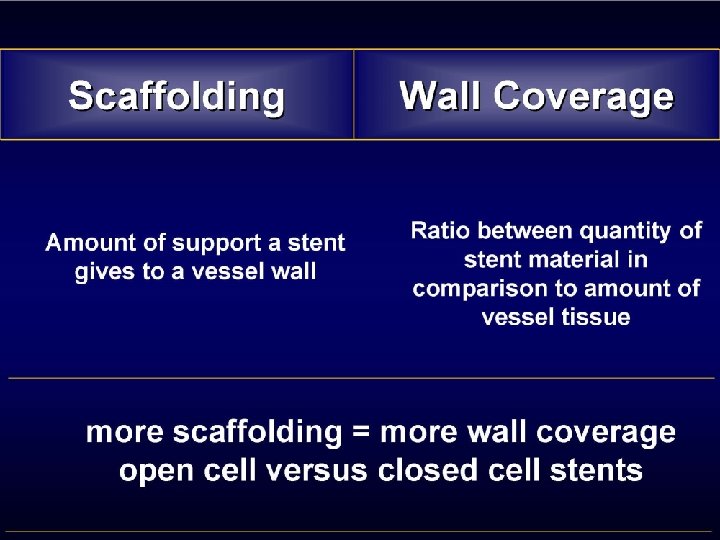

Conclusion • Different complication rates between stents • Almost entirely explained by symptomatic population • Late complication event rates are – Highest for the open cell types – Increase with increasing free cell area • Prospective randomised trials required to further investigate the importance of free cell area • For the time being, stents with a small free cell area should be used in symptomatic patients